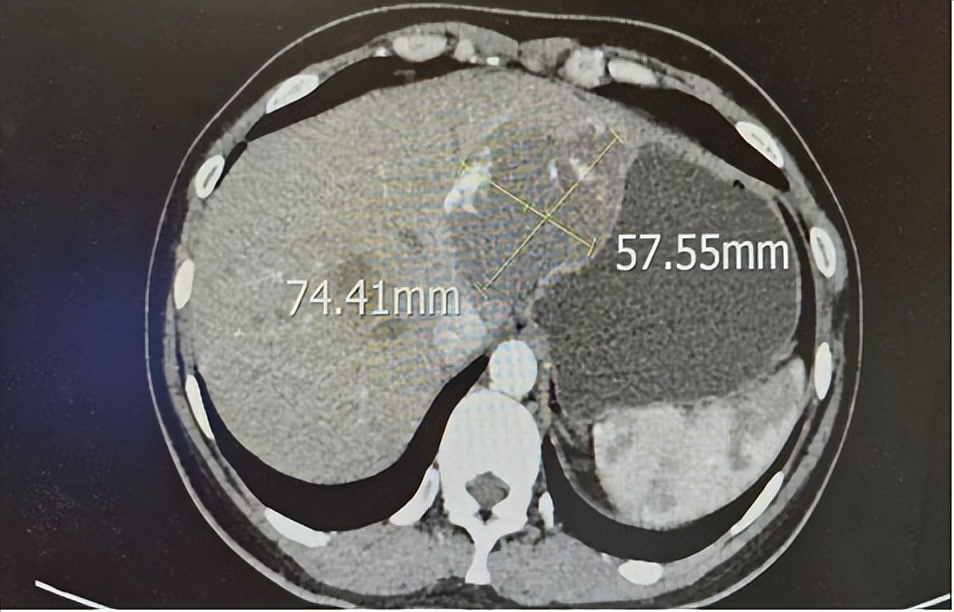

入院后,治疗团队完善相关检查,为其行腹部平扫+增强,检查结果提示:肝脏多发血管瘤,最大的一个直径已达到7.4cm,周边还有5个小一些的血管瘤。